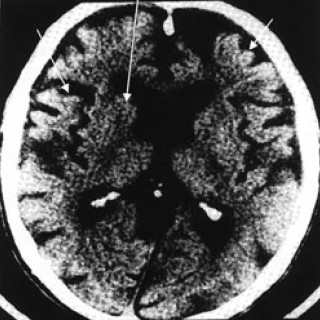

Demens med Lewy-legemer er en tilstand som i de senere årene har fått stor oppmerksomhet innen geriatri, nevrologi, psykiatri og nevropatologi. Symptombildet er variert og ofte dramatisk, med både motoriske, kognitive, psykiatriske og vegetative symptomer. Man vil derfor kunne møte pasienter med demens med Lewy-legemer både på indremedisinske, geriatriske, nevrologiske og psykiatriske sykehusavdelinger, på sykehjem og i allmennpraksis. Tilstanden er den nest hyppigste årsak til nevrodegenerativ demens, og pasientgruppen representerer derfor en stor og viktig utfordring for helsevesenet. I...